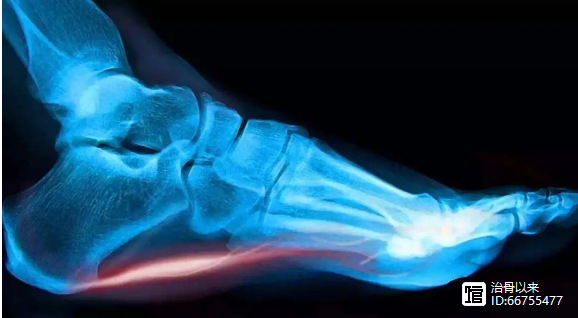

椎间盘相当于一个微运动关节,它由透明的软骨板,纤维环和髓核组成,分布在腰椎之间。由于脊髓穿过椎间盘的后部,因此当突出的椎间盘压迫脊髓神经或马尾神经导致腰痛或小便失禁甚至瘫痪时,这被称为腰椎间盘突出症。实际上,腰椎间盘突出症到来时会发出预警信号。

疼痛是腰椎间盘突出症发生的主要信号。 “当您触摸整个身体时,”腰部和腿部疼痛是组织受损的迹象。它告诉您组织已损坏并发炎。你要注意腰椎间盘突出症的生姜物理疗法的土方安排如下,供患者参考。